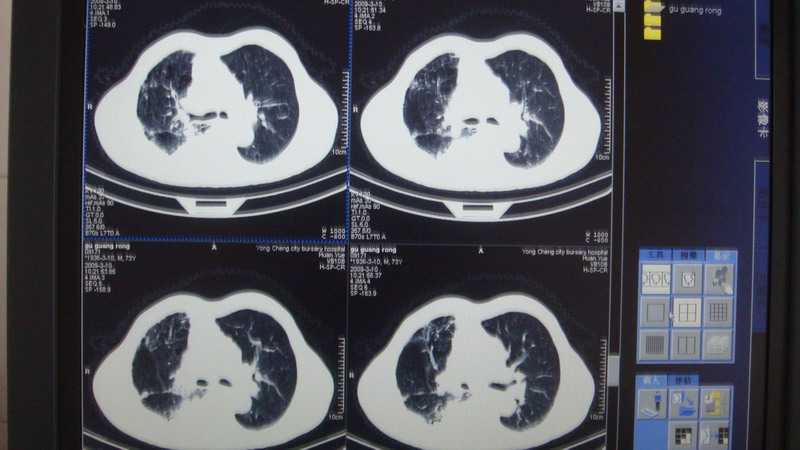

以下是引用光影相伴在2009-3-11 17:27:00的发言:[br]支持 右肺下叶周围型肺癌伴右肺门纵隔淋巴结转移;右上肺继发型肺结核(硬结\\纤维灶);右侧少量胸胸腔积液。另:不排除右侧胸膜转移可能。

以下是引用随光逐影在2009-3-11 16:57:00的发言:[br]支持 右肺下叶周围型肺癌伴右肺门纵隔淋巴结转移;右上肺继发型肺结核(硬结\\纤维灶);右侧少量胸胸腔积液。另:不排除右侧胸膜转移可能。

以下是引用草之原在2009-3-11 19:03:00的发言:[br]支持 右肺下叶周围型肺癌伴右肺门纵隔淋巴结转移;右上肺继发型肺结核(硬结\\纤维灶);右侧少量胸胸腔积液。另:不排除右侧胸膜转移可能。